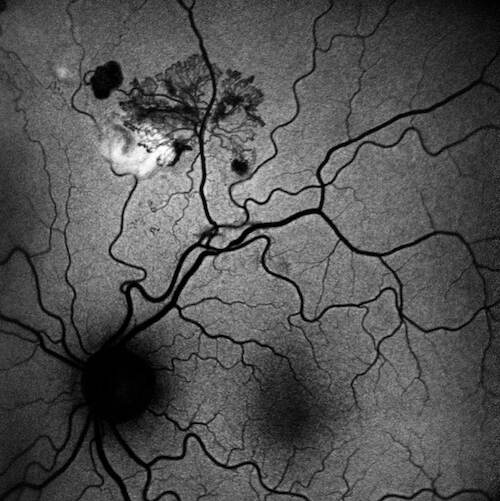

Fluorangiografia (FAG)

L’esame fluorangiografico ha confermato la natura ischemico-proliferativa del quadro:

- Fasi precoci: Rapida iperfluorescenza del complesso vascolare frondiforme.

- Fasi tardive: Marcato e progressivo leakage di colorante (staining e diffusione nei tessuti circostanti), inequivocabile segno di neovascolarizzazione retinica attiva.

- Ischemia: È ben delimitabile una vasta area di alterata/ridotta perfusione capillare retinica nel settore superiore, che funge da substrato ischemico primario per la proliferazione.

- Analisi degli shunt/collaterali: Gli shunt/collaterali vascolari apprezzati alla retinografia si confermano come vasi ad iperfluorescenza tardiva relativamente contenuta rispetto al complesso neovascolare principale, con pattern angiografico compatibile con canali vascolari di remodelling piuttosto che con neovasi attivi con leakage intenso. Questo pattern è in accordo con la letteratura che distingue i collaterali — caratterizzati da iperfluorescenza stabile senza leakage marcato — dai neovasi — caratterizzati da leakage progressivo nelle fasi tardive3.

È essenziale notare l’assenza di staining diffuso della parete vascolare o di segni di perivasculitis (come il fern-like leakage), che rende altamente improbabile l’ipotesi di una vasculite retinica in fase attiva. Allo stesso modo, non si rilevano dilatazioni sacciformi o fusiformi tipiche del macroaneurisma arterioso, escludendolo come lesione patogenetica primaria.

| FAG | Area di non-perfusione superiore. Leakage tardivo marcato dal ciuffo neovascolare. Iperfluorescenza contenuta degli shunt. Assenza di staining vasale diffuso. | Ischemia retinica settoriale con NVE (neovascolarizzazione altrove) attiva. Esclusione di vasculite diffusa e macroaneurisma. |